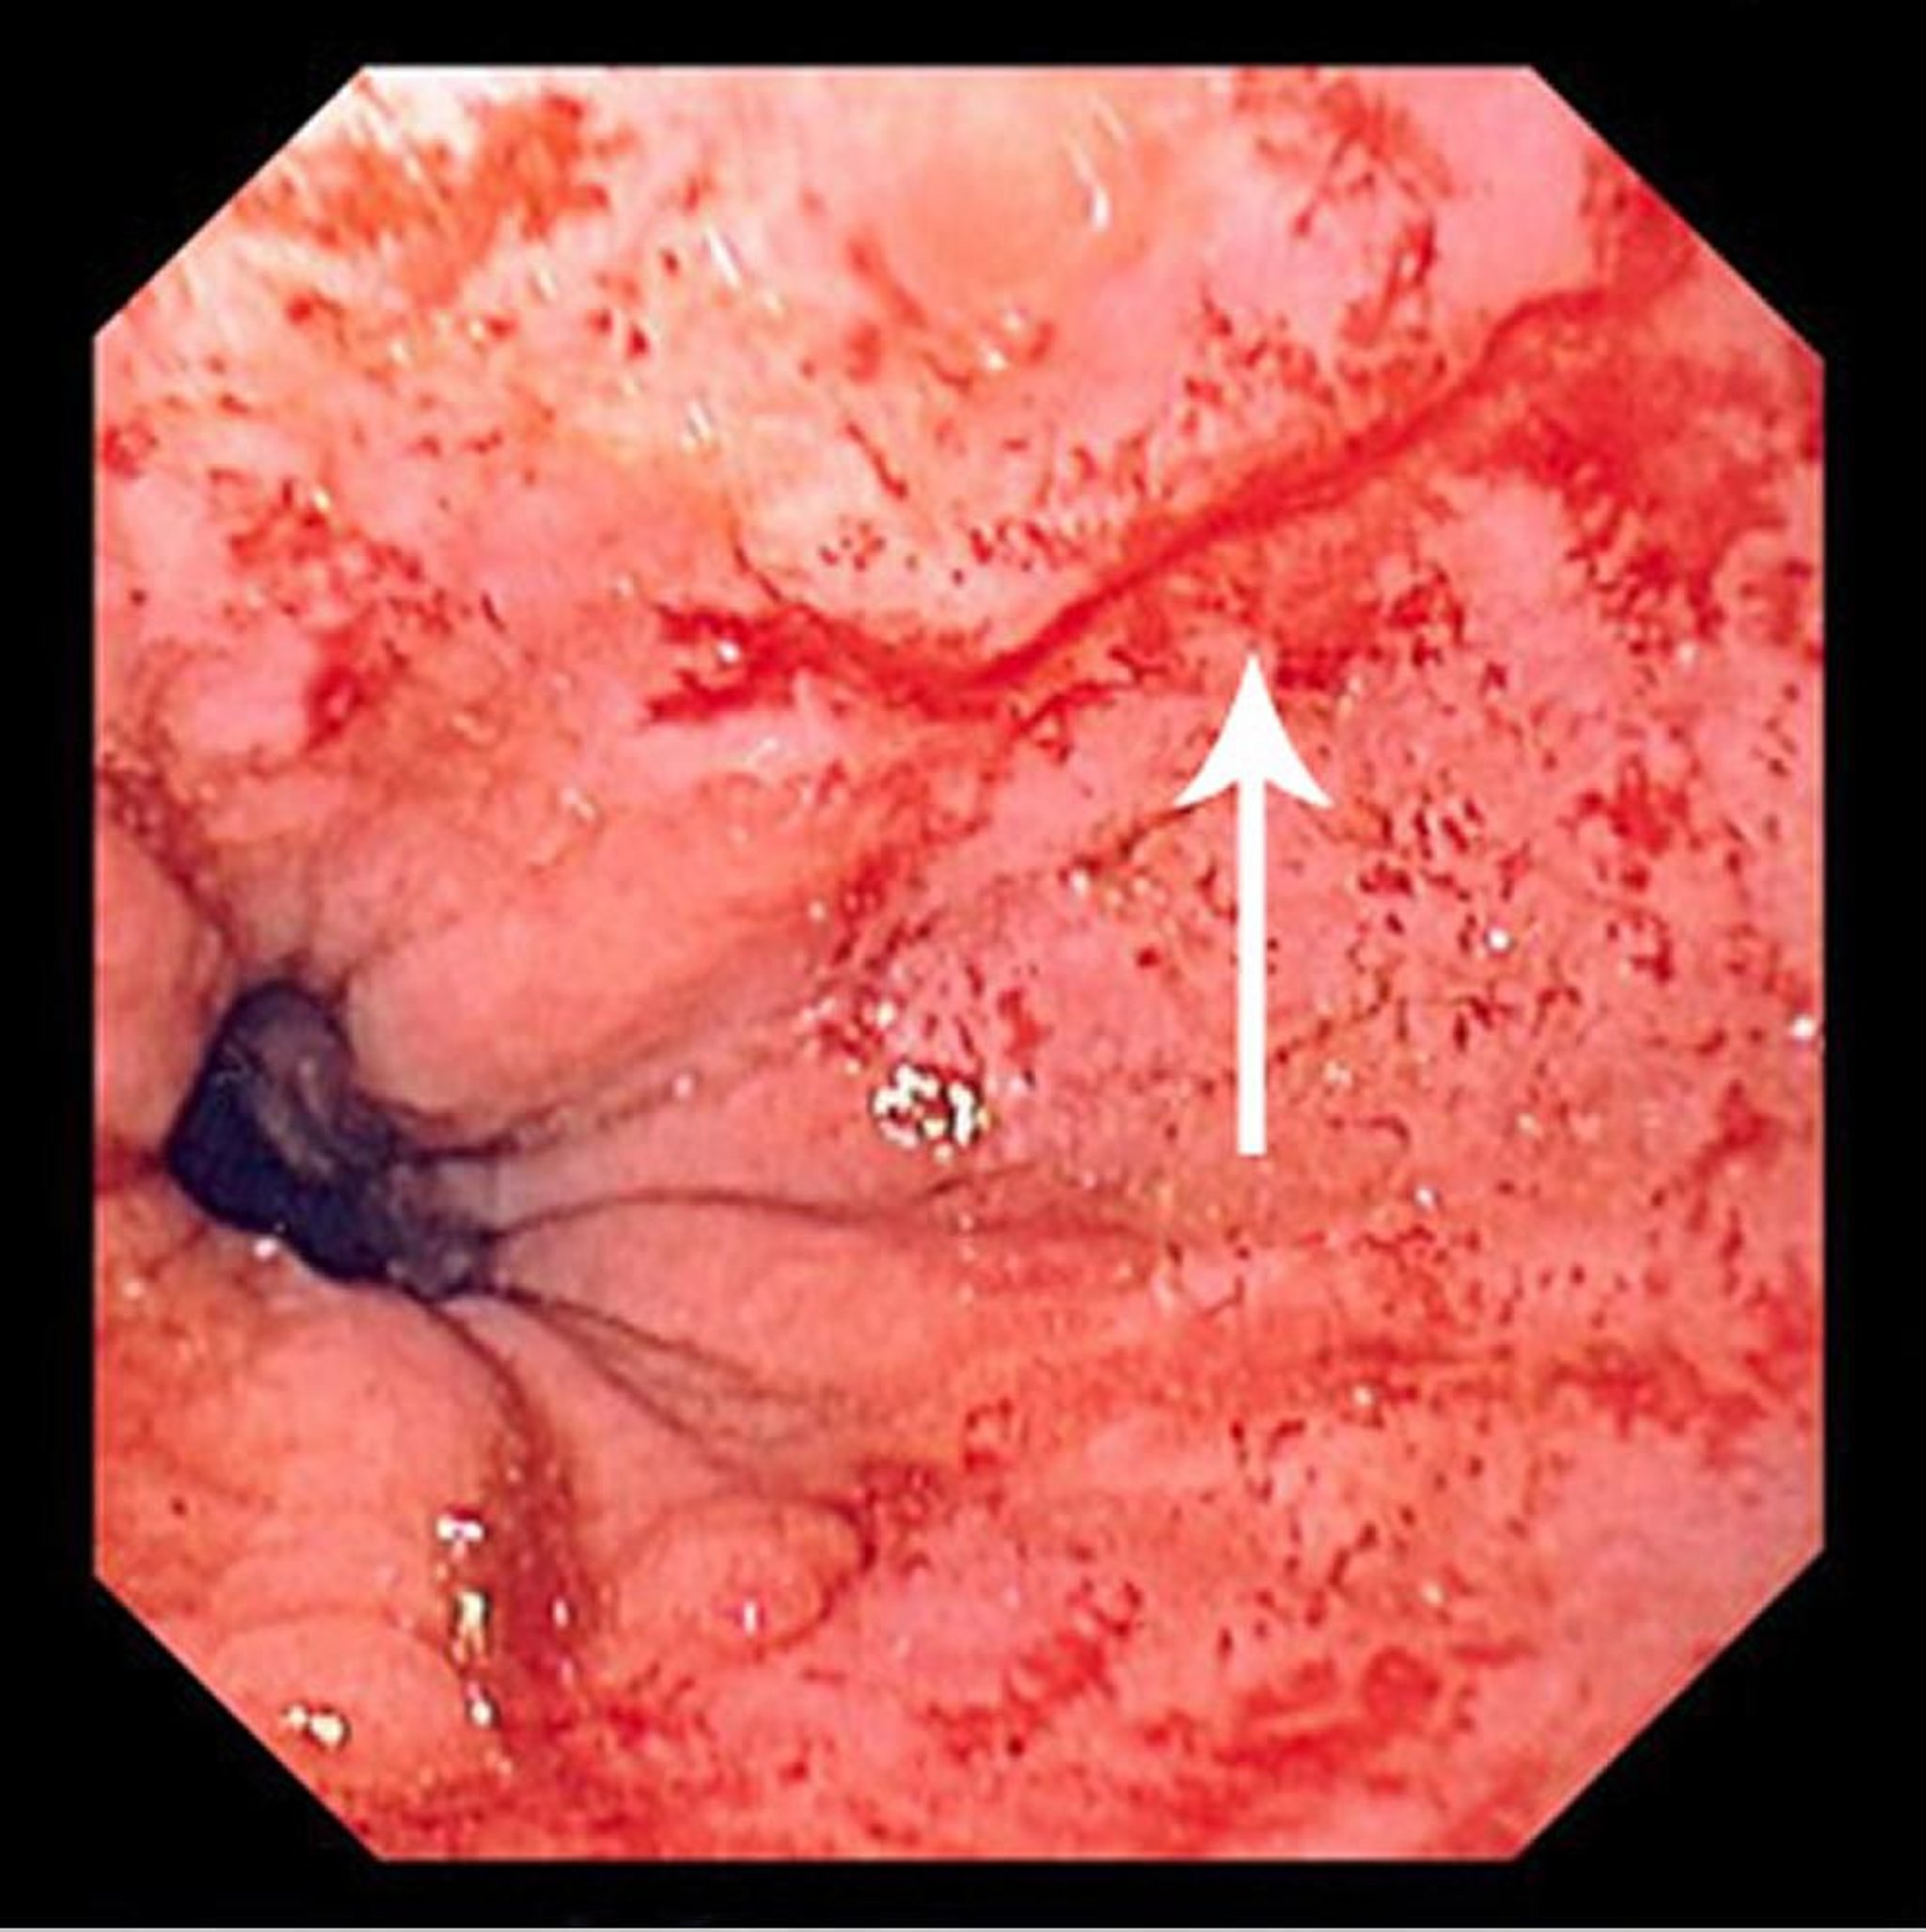

Desgarro de Mallory-Weiss

Esta foto muestra un fino desgarro de Mallory-Weiss (flecha).

Foto proporcionada por David M. Martin, MD.